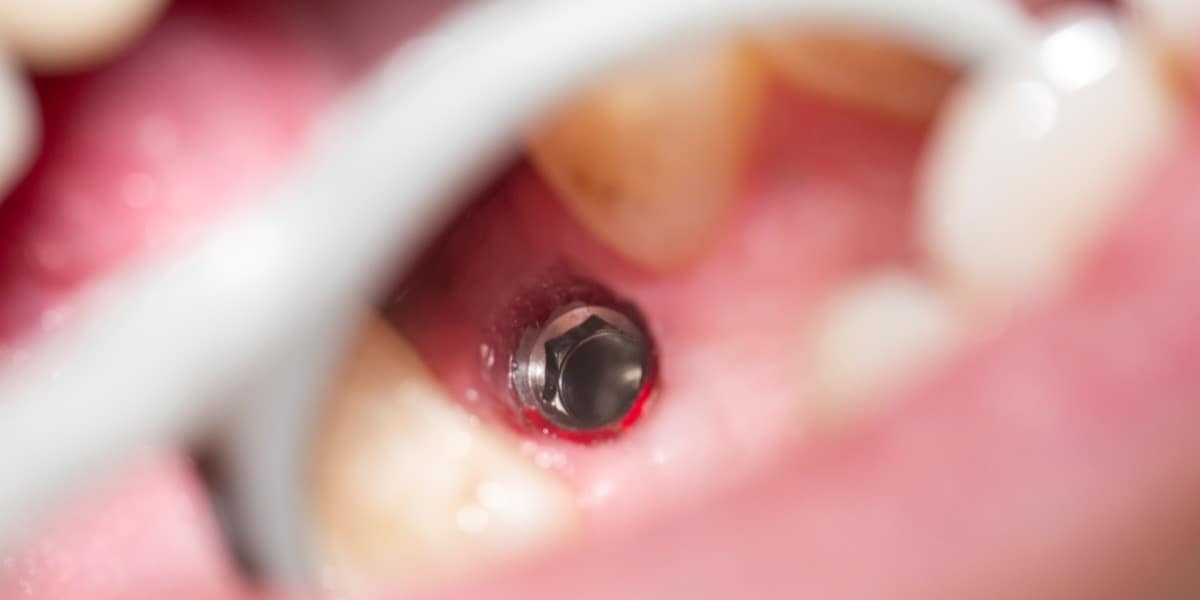

Zubní implantát je alternativním protetickým řešením, neboť chybějící zuby lze kromě klasického můstku klinicky vhodněji nahradit zubním implantátem, který splňuje všechny funkce původního zubu a navíc je jeho přirozenou a věrnou kopií, bez nutnosti zbrousit (degradovat) jiné okolní zuby (jako v případě můstku).